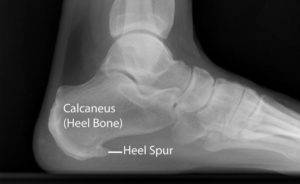

ΑΚΑΝΘΑ ΠΤΕΡΝΑΣ

Η άκανθα είναι μια οστεώδη ανάπτυξη στην πρόσθια και κάτω επιφάνεια της πτέρνας και συναντάται στο 15% του γενικού πληθυσμού με αυξημένη συχνότητα στους ηλικιωμένους, υπέρβαρους, ασθενείς με ΠΑ, οστεοαρθρίτιδες, ρευματοειδή αρθρίτιδα και εμβιομηχανικές ανωμαλίες του άκρου ποδός.

Οι άκανθες πτέρνας αποτελούν αποτέλεσμα της πελματιαίας απονευρωσίτιδας και όχι αιτία για την δημιουργία της. Το επαναλαμβανόμενο τραύμα, εμποδίζει την σωστή διαδικασία επούλωσης δημιουργώντας μια χρόνια κατάσταση φλεγμονής και οστεοποίηση του ουλώδη ιστού, με αποτέλεσμα την δημιουργία άκανθας στο έσω φύμα της πτέρνας. Η απεικόνιση της άκανθας γίνεται μέσω απλής ακτινογραφίας, καθώς και με μαγνητική τομογραφία.

Εικόνα 1: Άκανθα πτέρνας (https://orthoinfo.aaos.org/en/diseases–conditions/plantar-fasciitis-and-bone-spurs)